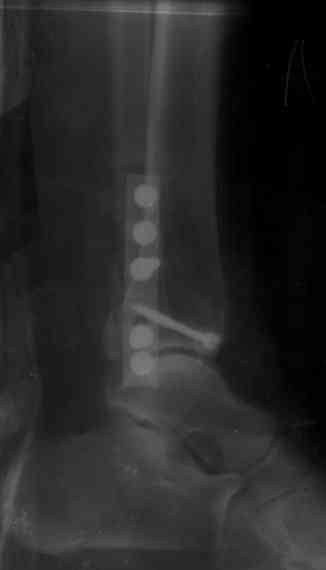

Re: Перелом обеих лодыжек и з/края б/б кости с выв

После проведенной дискуссии пришел к выводу, что трансартикулярная диафиксация не совсем приемлима с учетом современных методик остеосинтеза. Кроме того, вычитал, что хрящ разрушается на расстоянии до 0,5 см от места проведения спицы.

Пока я был в интернатуре, предпочитали осуществлять стабильный остеосинтез с ранней функцией. См. приложения и полнотекстный вариант

статьи.